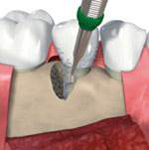

- Uzavřený, interní, vnitřní, crestální sinus lift

Více - Používané přístroje, technologie, materiály

CAS Kit

Souprava pro krestální přístup k operaci sinus liftu tím, že se vytvoří v kosti kónický odštěpek, kterým lze membránu bezpečně nadzvednout.